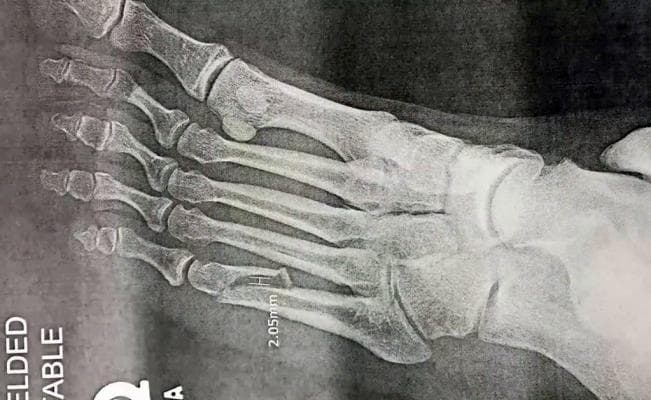

¡Hoy se ve así! El cantante ha engordado muchísimo de un tiempo para acá y justo en el arranque de las pocas fechas que darán, él se rompió un dedo del pie, por lo que tuvo que salir a escena con un yeso (negro muy rocker) y estuvo en una silla de ruedas ... de "metal".

Ouch! El artista tuvo que ser intervenido debido a la fractura en el pie izquierdo.

En un video que compartieron en sus redes sociales, la doctora que lo intervino explicó de qué se trata la lesión.